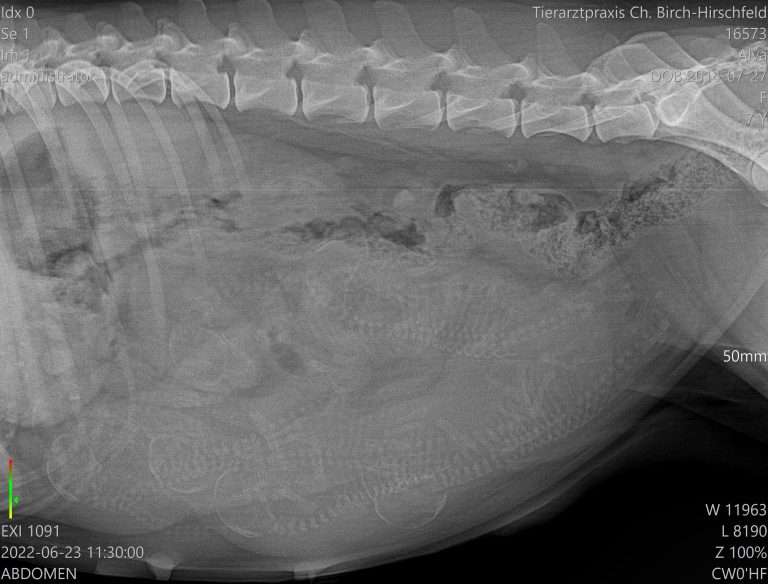

56. Trächtigkeitstag A-Wurf Der Tierarzt unseres Vertrauens hat unserer Alva nicht nur beste Konstitution bescheinigt, sondern auch das erste offizielle Bild der frechen Freckles gemacht.